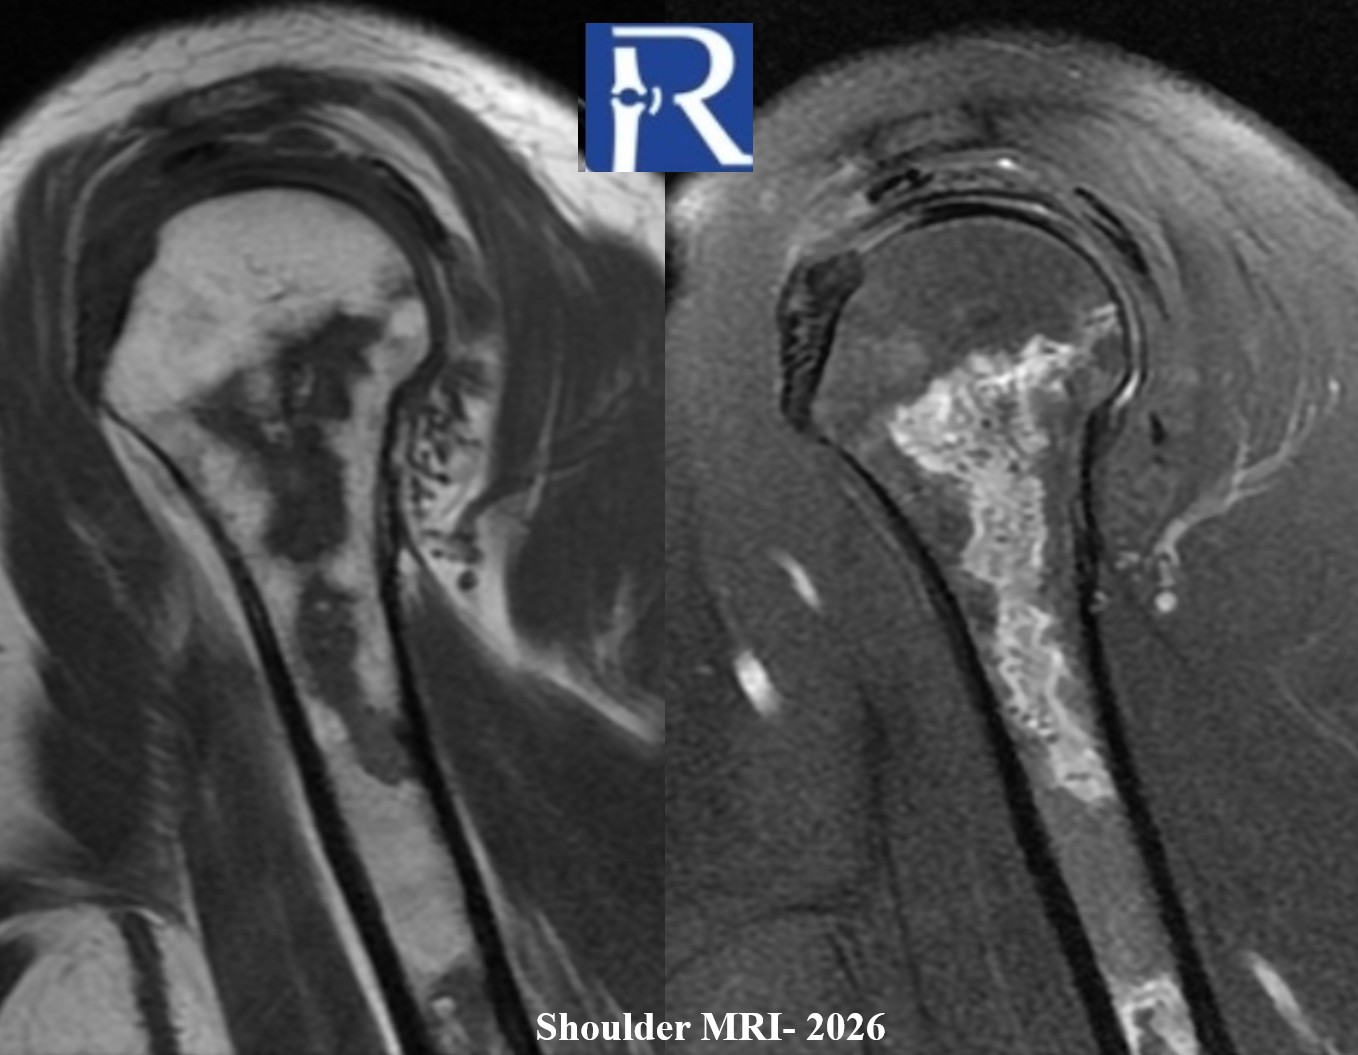

- Current MRI demonstrates a better defined medullary lesion with a geographic pattern and signal characteristics in keeping with medullary osteonecrosis.

- In this case, serial imaging shows evolution from ill-defined marrow signal change to a geographically delineated medullary lesion, supporting the diagnosis of steroid-associated medullary osteonecrosis rather than a neoplastic process. CT adds value by demonstrating peripheral or matrix mineralization, which may be observed in chronic osteonecrotic lesions

- Multimodality imaging (XR → CT → MRI) enhances diagnostic confidence, particularly in distinguishing ischemic necrosis from neoplasia.

- Temporal progression of findings contributes valuable diagnostic insight, especially when prior imaging is available.